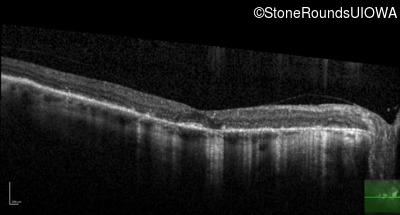

Age at visit: 62 years

This 62 year old man first noted mild distortion in his vision in his 30's, but has always been correctable to 20/20. One year ago an optometrist told him there were pigment abnormalities in his macula.

Diagnosis & molecular findings

Disease Gene Allele 1 variant(s) Allele 2 variant(s) Inheritance mode

Pattern Dystrophy PRPH2 Lys153Glu AAG>GAG   AD